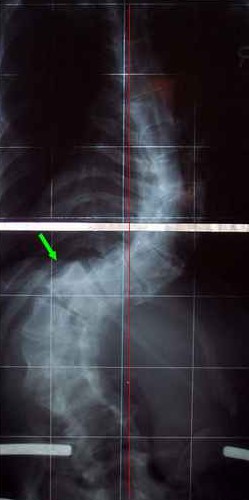

Nicht ersckrecken, unten hier ist ein Beispiel, wie eine Skoliose mit 93° und 98° aussehen KANN.

Dateianhänge

Skoliose mit 93° und 98°

skoliose.jpg (22.53 KiB) 11981 mal betrachtet